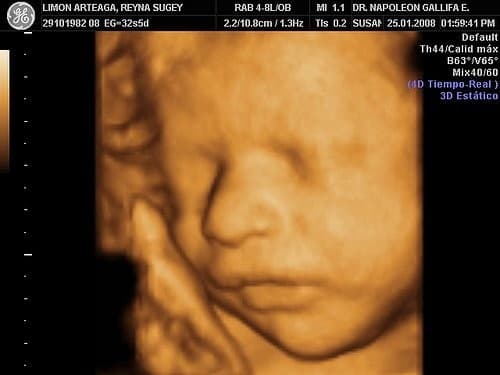

Siêu âm thai 4D là hình thức siêu âm cho phép ghi lại hình ảnh của thai nhi đang chuyển động trong thời gian thực. Khi máy siêu âm quét trên bụng mẹ, những hoạt động của bé như bé nhúc nhích, đạp, nhăn mặt, mút ngón tay, nhép miệng,… sẽ được hiển thị rõ nét trên màn hình siêu âm.

Siêu âm thai 4D ghi lại những hình ảnh chuyển động rõ nét của thai nhi.

Từ hình thức siêu âm 4D, bố mẹ nhìn rõ hơn khuôn mặt, làn da, các bộ phận trên cơ thể bé, sự chuyển động của bé. Đây là điều tuyệt vời, tạo sự liên kết đặc biệt giữa bố mẹ và con yêu trong bụng, và giúp bác sĩ nhìn rõ sự phát triển của thai nhi, phát hiện những bất thường (nếu có) của thai nhi.

Khuôn mặt, làn da, các bộ phận trên cơ thể bé, sự chuyển động của bé… mẹ có thể nhìn thấy rõ ràng hơn.